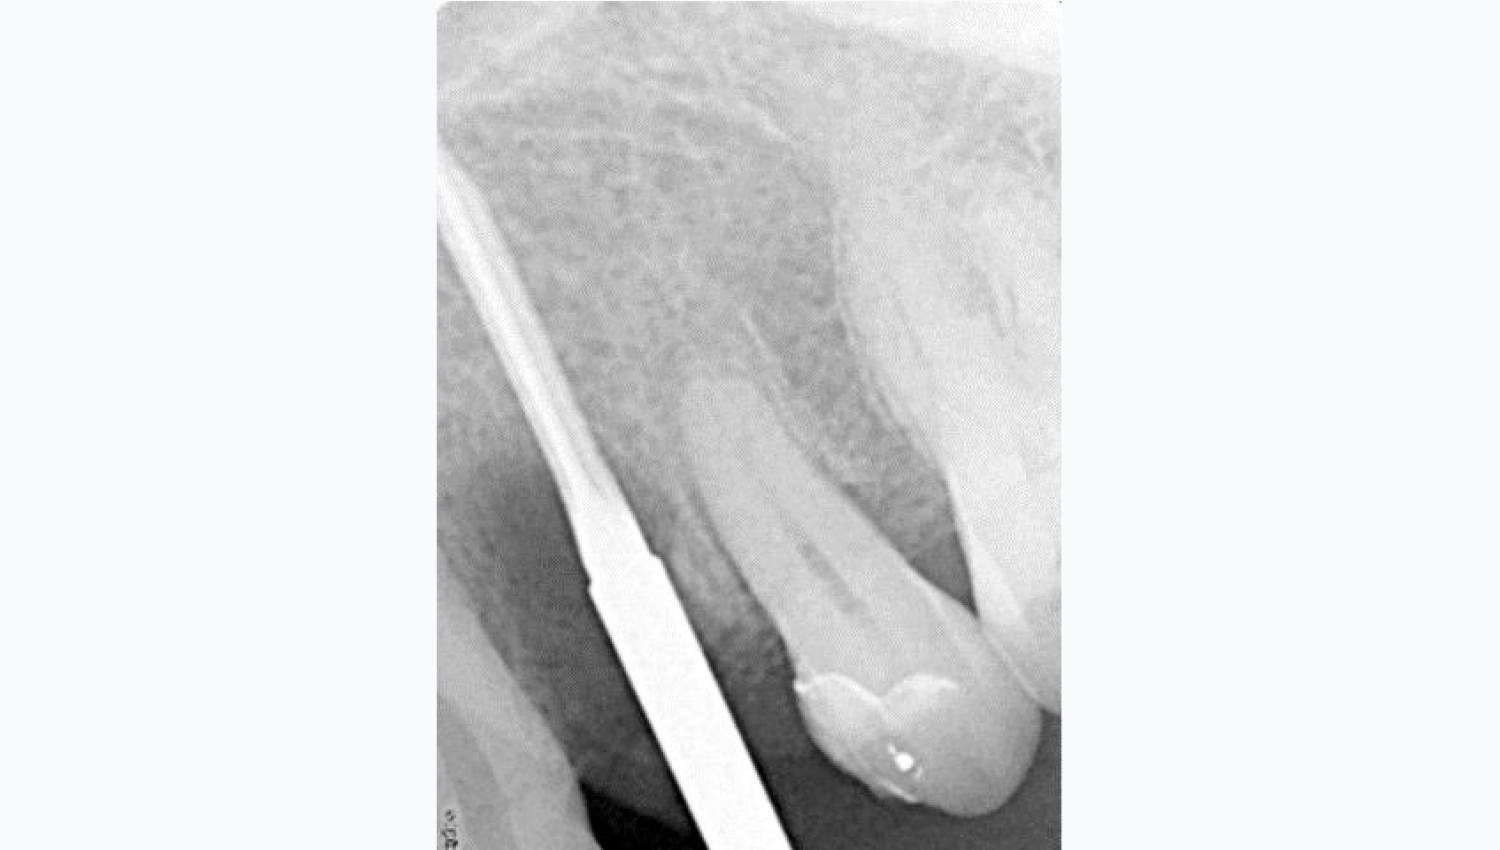

1.Initial radiological view.